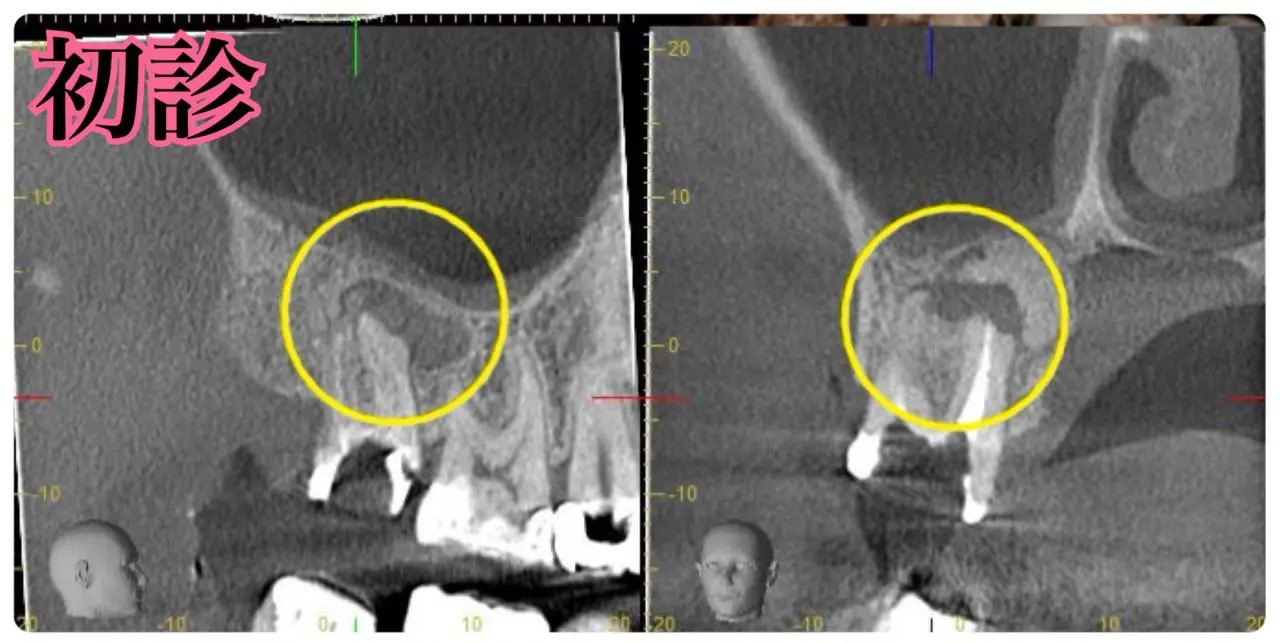

診断:CTによる精密検査で見つかった複雑な感染源

CTでしっかりと診断を行ったところ、とても深刻な状況でした。根管治療が重要ですが、それだけでは完全な治癒が望めない場合もあり、歯槽骨の再生を促す外科的処置が必要になることもあります。

こちらの患者様のように、歯槽骨のダメージが大きい症例では、根管内の感染と歯肉溝内の感染が両方の原因となっていることが多いですね。

根尖病変によりCT上で黒く写っていた部分が白っぽくなっているのがわかりますか?

溶けていた部分の歯槽骨が回復しているということです!

また、上顎洞の肥厚は収まり、頬側の歯槽骨もくっきり映っています。予想以上に歯槽骨が回復しているので、今後外科的処置をしなくても良いのではないかと判断しました。大きなダメージがあった歯なので補綴物を入れた後も欠かさずに経過観察を行い、少しでも長くご自身の歯で生活して頂きたいと思います。